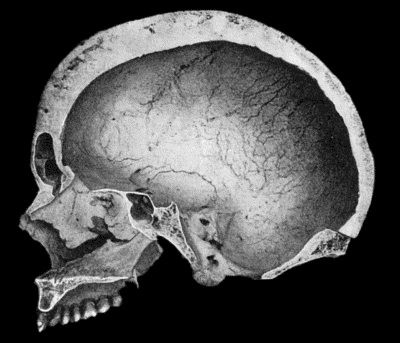

470 134.Changes in the Skull resulting from Ostitis Deformans

474 135.Cadaver, illustrating the alterations in the Lower Limbs resulting from Ostitis Deformans